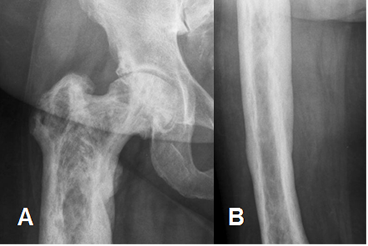

Fig 49. Enfermedad de Paget en fase mixta.

A: Rx AP de cadera y B: Rx AP de fémur. Hueso aumentado de tamaño, con engrosamiento de la cortical e incremento de su trabeculación.